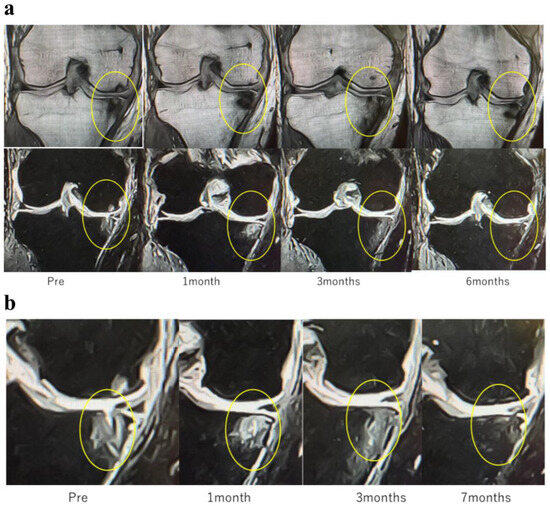

These findings indicate that SBP tear plays a decisive role in BML severity and pain mechanisms, suggesting its importance as a pathological marker in designing knee OA treatment strategies based on BMLs. Consequently, in our conservative treatment strategies targeting subchondral bone, we have prioritized the presence or absence of SBP tear and joint surface collapse (Figure 2a,b and Figure 3a,b).

Figure 3.

MRI findings of (a) femoral articular surface collapse in the knee joint and (b). (a) Representative MRI images on T1-weighted and T2-weighted sequences (coronal and sagittal planes) are shown. In the area indicated by yellow circles, the articular surface exhibits marked irregularity with loss of cartilage continuity. At the sites indicated by red arrows, SBP disruption and cortical collapse are evident, demonstrating structural failure of the articular surface. Furthermore, on T2-weighted images, joint fluid signals extend into the bone marrow, suggesting the presence of bone marrow lesions (BML) and edematous changes within the subchondral bone. (b) MRI findings demonstrating tibial articular surface collapse. Coronal and sagittal T1- and T2-weighted MRI images are presented. In the regions outlined by yellow circles, the tibial articular surface exhibits marked irregularity, and at the sites indicated by red arrows, evident loss of continuity of the SBP is observed with cortical depression and collapse of the articular surface. On T2-weighted images, the hyperintense joint fluid signal extends into the bone marrow, suggesting the presence of BMLs and associated edematous changes.